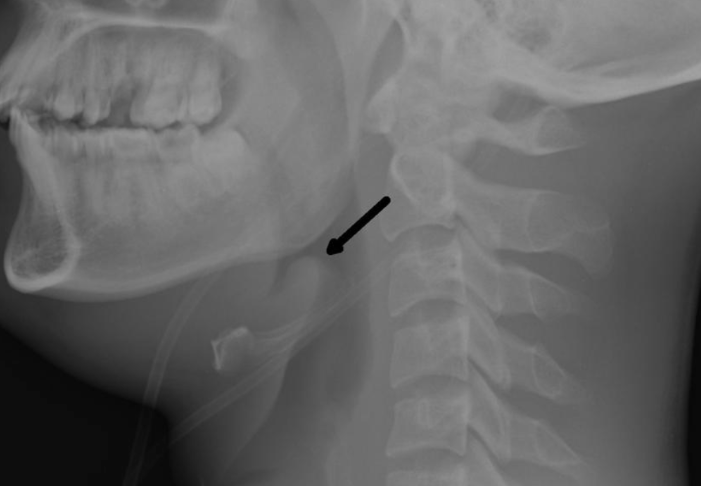

- “Thumb sign” en RX profil